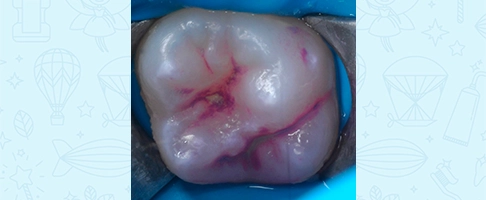

Герметизация фиссур постоянного зуба